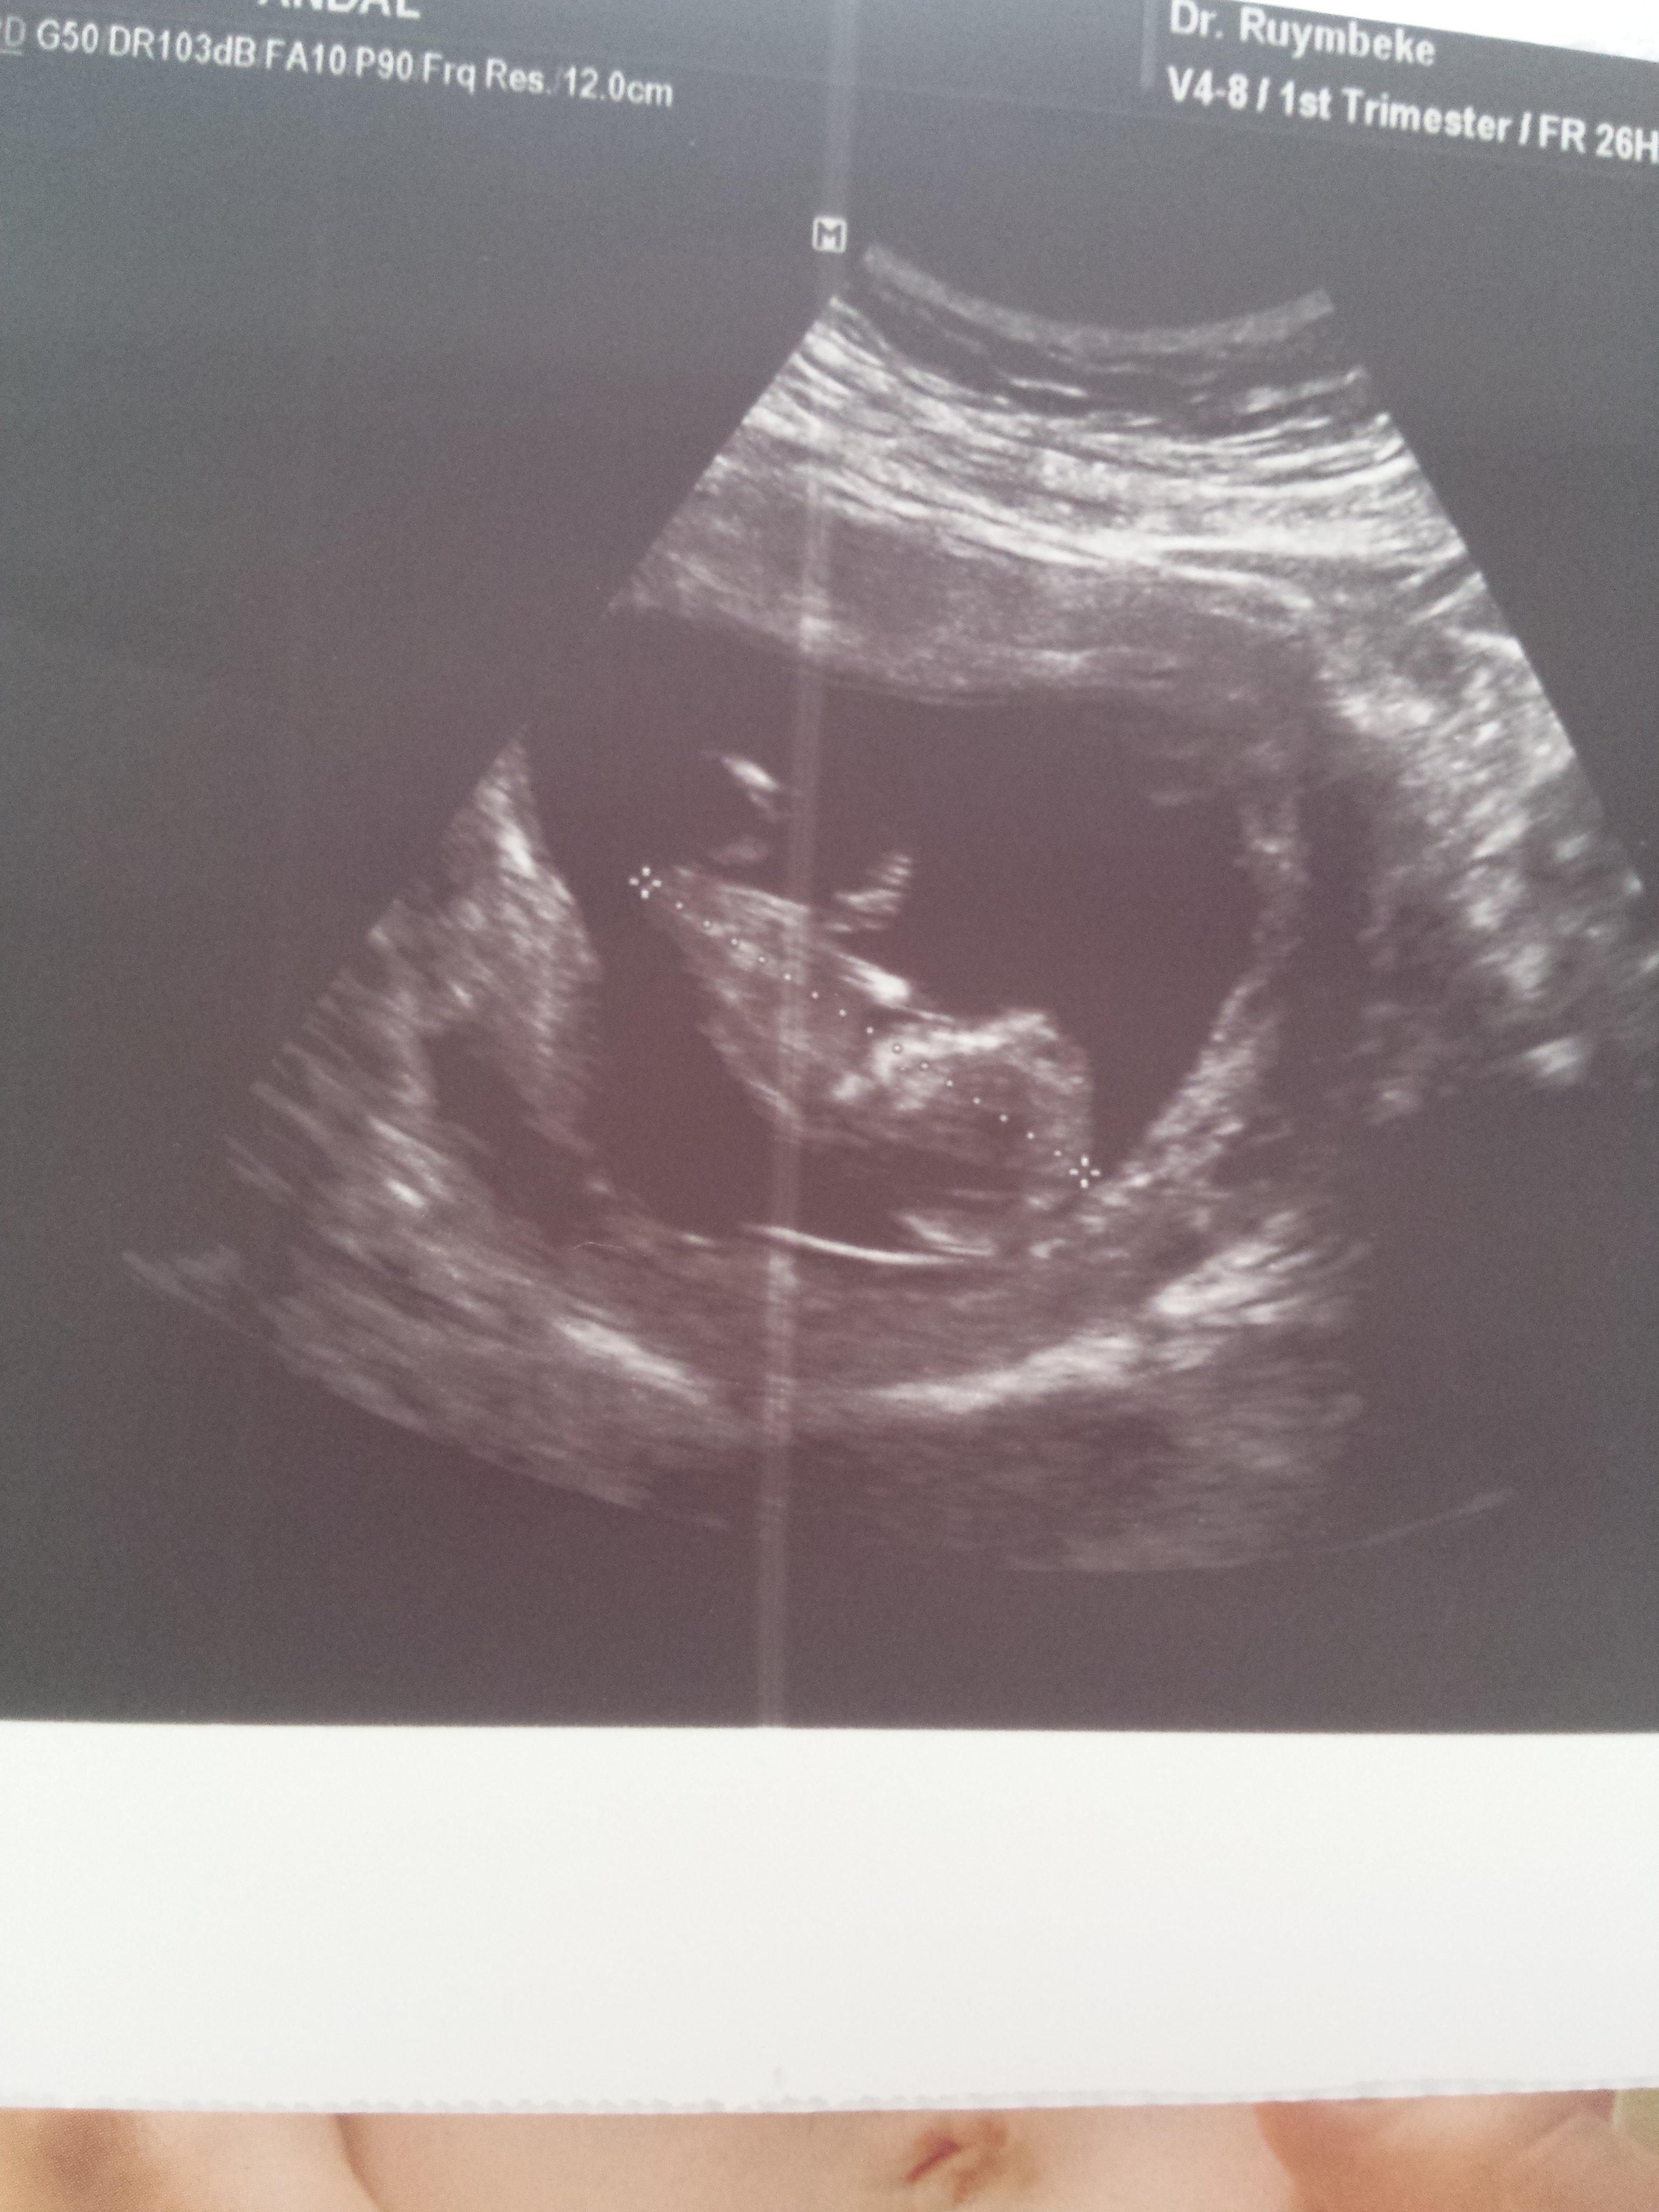

1 1234tmm Yeni Üye Üye 29 Nisan 2017 #266 Ekli dosyayı görüntüle 76265 11+4 dusuncelerinixi alabilirmiyim *BEYZA*' Alıntı: Yorum yaptığınız yerde fotoğraf yükle butonu var.Yüklemeyi ordan yapıcaksınız. Genişletmek için tıkla ... Cok tesekkur canim sanirim oldu.

Ekli dosyayı görüntüle 76265 11+4 dusuncelerinixi alabilirmiyim *BEYZA*' Alıntı: Yorum yaptığınız yerde fotoğraf yükle butonu var.Yüklemeyi ordan yapıcaksınız. Genişletmek için tıkla ... Cok tesekkur canim sanirim oldu.

Uzman SühaN Administrator 29 Nisan 2017 #267 Merhaba, Nub çıkıntısı pek net değil fakat bebeğinizin cinsiyetinin kız olduğunu düşünüyorum.Sağlıklı gebelik geçirmeniz dileği ile.

Merhaba, Nub çıkıntısı pek net değil fakat bebeğinizin cinsiyetinin kız olduğunu düşünüyorum.Sağlıklı gebelik geçirmeniz dileği ile.